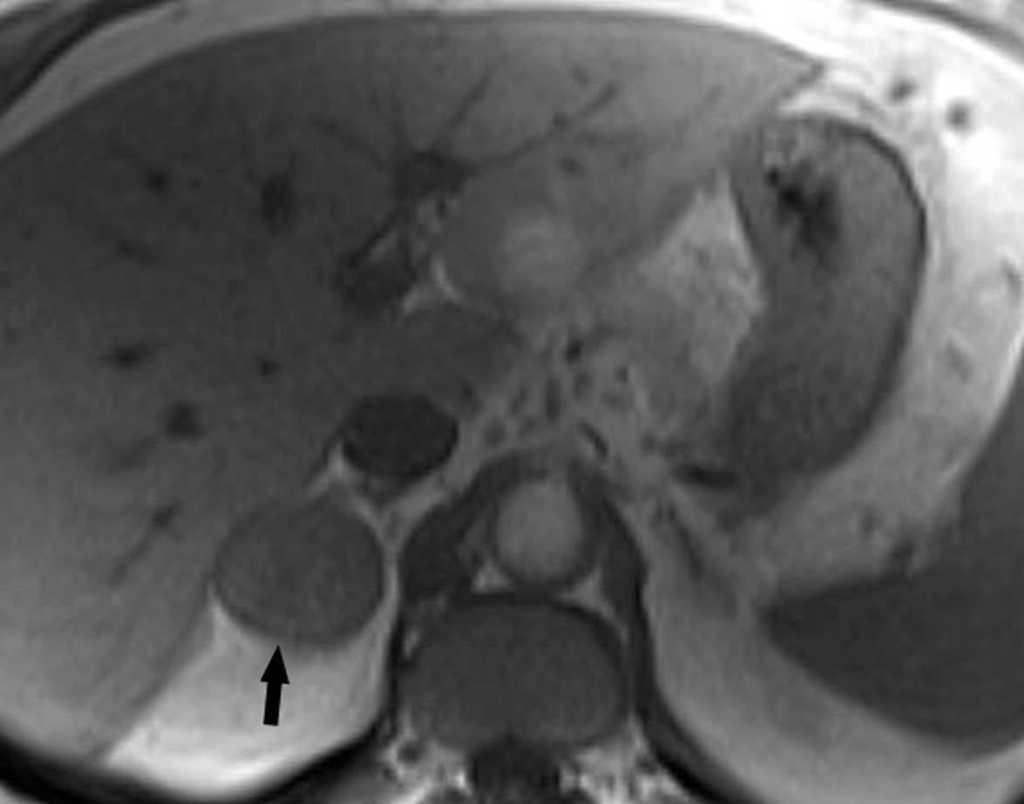

La aparición de nódulos suprarrenales se da en más del 10% de los pacientes con cáncer de pulmón. Dada la elevada frecuencia de adenomas benignos, es crucial la distinción entre éstos y la afectación metastásica. Ésta se puede llevar a cabo con una combinación de estrategias de imagen que incluyen TC, RM y/o PET. Por TC los adenomas suprarrenales típicamente tienen valores de atenuación bajos por la presencia de cúmulos lipídicos. Una lesión suprarrenal con valores de atenuación menores de 10 unidades Hounsfield (UH) en el estudio sin contraste, tiene una probabilidad del 98% de que se trate de una lesión benigna. Dado que ambas lesiones, adenomas y metástasis captan contraste, la valoración rutinaria de la captación no es útil en la diferenciación entre benignidad y malignidad. Si se detecta durante la realización de la TC, realizar cortes tardíos a los 15 minutos de la administración de contraste es importante, ya que si existe un lavado del contraste de más del 50% el diagnóstico de adenoma tiene una sensibilidad del 98% y una especificidad que oscila entre el 92 y el 100%20. La RM con secuencias de desplazamiento químico en la valoración de nódulos suprarrenales tiene una especificidad del 100% para el diagnóstico de adenoma (fig. 14). Sin embargo, la sensibilidad depende de la densidad de la lesión en el estudio con TC, ya que cuanto mayor es la densidad en la TC menos señal perderá en la RM, con lo que resulta más difícil etiquetarlo como adenoma21. La PET presenta una sensibilidad alta en la detección de metástasis suprarrenales, ya que cuando una lesión suprarrenal no muestra signos concluyentes en la TC de benignidad, la ausencia de actividad con la PET hace muy probable dicho diagnóstico. En los casos en que persistan dudas diagnósticas se debe recurrir a la biopsia de la lesión adrenal, especialmente si de este diagnóstico depende el manejo del paciente.

Fig. 14.--Lesión suprarrenal. (A) Tomografía computarizada (TC) abdominal sin contraste que muestra un nódulo suprarrenal derecho de baja atenuación y contornos bien definidos (flecha). (B) Con contraste se aprecia captación del mismo. (C) Resonancia magnética (RM) en fase en la que se identifica el nódulo suprarrenal isointenso con el hígado. (D) En la RM fuera de fase, se pone de manifiesto la pérdida de señal (marcadamente hipointensa con respecto al hígado) característica de estos tumores suprarrenales debido a su contenido lipídico.